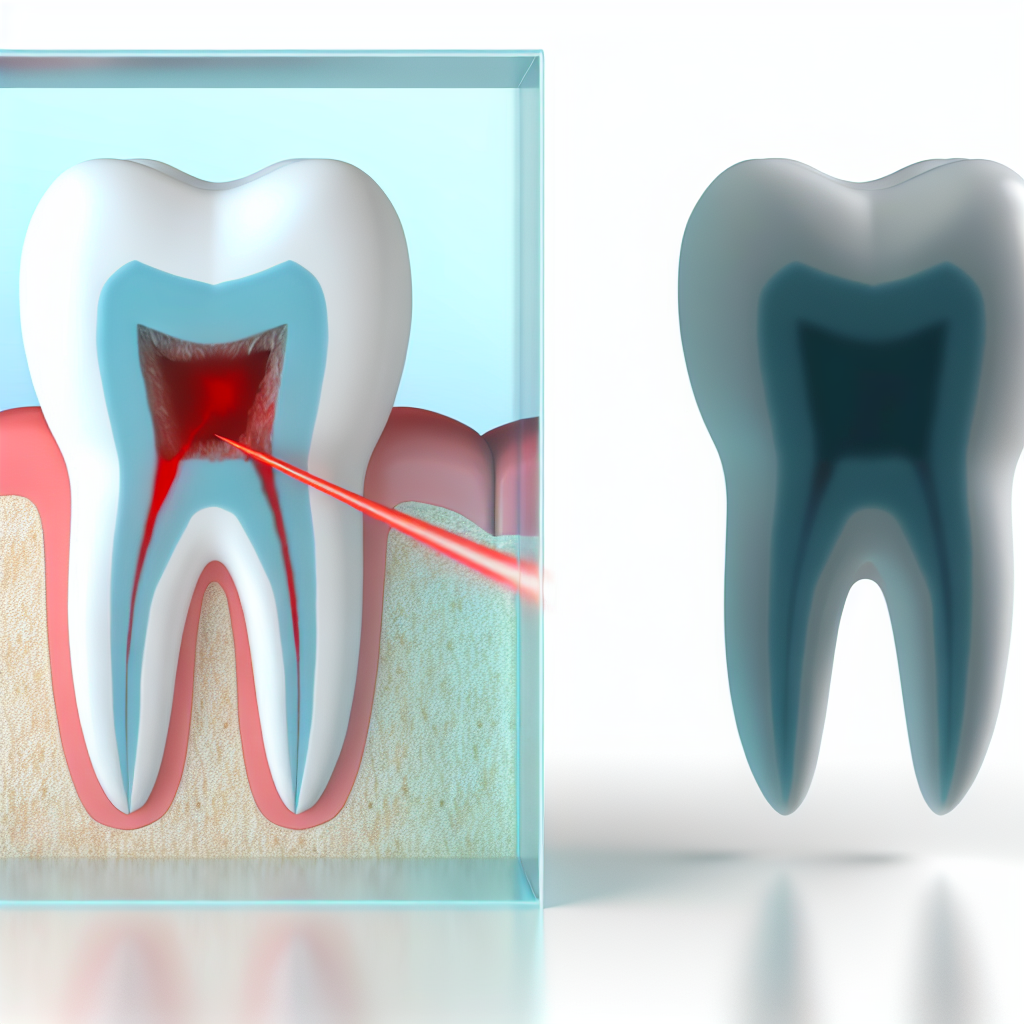

La estructura de un diente es más compleja de lo que parece. La capa externa, el esmalte, no tiene terminaciones nerviosas. Cuando la caries comienza ahí, es completamente silenciosa. El problema surge cuando esta lesión logra atravesar el esmalte y llegar a la dentina, una capa más blanda y sensible.

Sin embargo, incluso en esta etapa, el dolor puede ser intermitente o confundirse con sensibilidad. El verdadero dolor dental intenso y constante suele aparecer cuando la infección bacteriana alcanza la pulpa dental, donde se encuentran los nervios y vasos sanguíneos. Para entonces, la caries está muy avanzada y las opciones de tratamiento se reducen, frecuentemente requiriendo una endodoncia para salvar la pieza. La ausencia de dolor, lejos de ser una buena noticia, puede significar que el daño está progresando sin obstáculos.

Un caso común en la consulta es el de pacientes que presentan una pequeña mancha oscura en un molar. A simple vista, parece una caries superficial. Sin embargo, al tomar una radiografía, se revela que la caries ha avanzado horizontalmente por debajo del esmalte sano, creando una cavidad extensa en la dentina. Este “efecto iceberg” es la razón por la cual la exploración clínica combinada con imágenes radiográficas es irremplazable. Detectar esto a tiempo permite un tratamiento conservador con un empaste; dejarlo pasar, muy probablemente conduciría a la necesidad de una endodoncia.